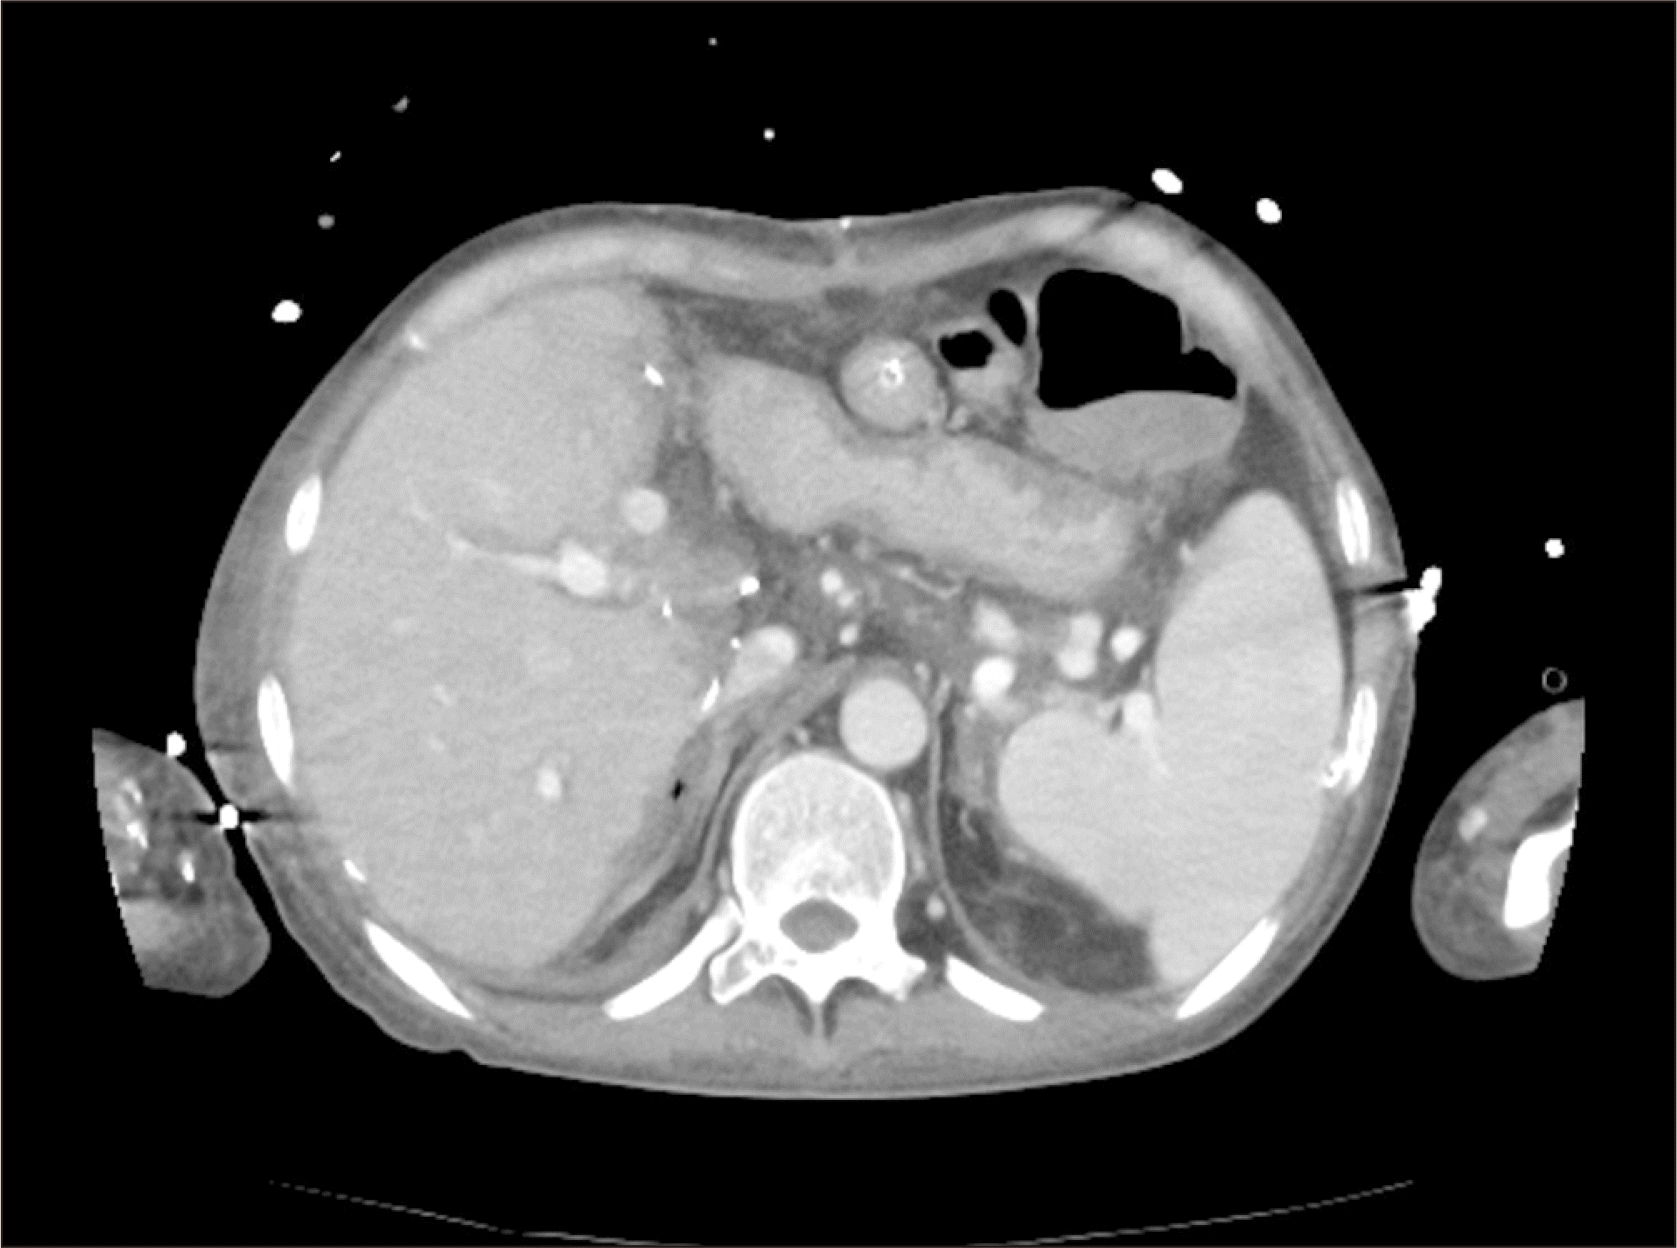

A 43-year-old female patient was diagnosed with acute on chronic liver failure associated with alcoholic liver cirrhosis (Fig. 1) with hyponatremia, and hepatic encephalopathy Grade 3 (Glasgow Coma Scale, GCS 10). Her medical history included partial gastrectomy for obesity in 2002. The patient underwent LDLT. Before transplantation, Rituximab infusion and one session of plasmapheresis were performed due to high titer of cytotoxic antibody. Sodium level was 125 mmol/L, and ammonia level was 231 mmol/L at the time of admission. GCS was 10. Sodium benzoate 4 g/20 mL and lactulose were initiated to decrease ammonia levels in the blood and improve mental status. Ammonia levels started decreasing after sodium benzoate and lactulose treatment, accompanied by slight improvement in mental status. One day before surgery, ammonia levels decreased from 231 mmol/L to 110 mmol/L (Fig. 2), while sodium levels increased from 125 mmol/L to 158 mmol/L. During surgery, a significant blood transfusion was performed, consisting of 8 L blood components - 12 units of red blood cell and 7 units of fresh frozen plasma. Sodium levels during surgery ranged from 150–153. Reperfusion caused severe bradycardia (heart rate 20), corrected by epinephrine 100 mcg IV. Post-LT, the patient was transferred to the intensive care unit. In postoperative period, liver doppler and liver function tests were normal, and postoperative liver computed tomography (CT) scan at postoperative 5th day showed normal findings (Fig. 3). Despite this, the patient remained unresponsive to commands and exhibited a tendency to sleep. Post-surgery ammonia levels decreased to 110 with a declining trend and normalized on post-operative day (POD)#2–3 (Fig. 2). However, the patient’s mental status deteriorated, with GCS score decreasing from 10 to 6. Sodium levels initially increased to 160 but normalized after POD#5. Electroencephalogram showed delta slowing, and Brain CT scan revealed no significant abnormalities. Magnetic resonance imaging (MRI)+diffusion-weighted imaging revealed CPM (Fig. 4). Conservative treatment was initiated, maintaining tacrolimus levels below 5 to prevent CPM progression, and vitamin B (thiamine) supplementation was provided. Levodopa was administered, resulting in improvement in mental status and GCS from 6 to 12 after POD#19.